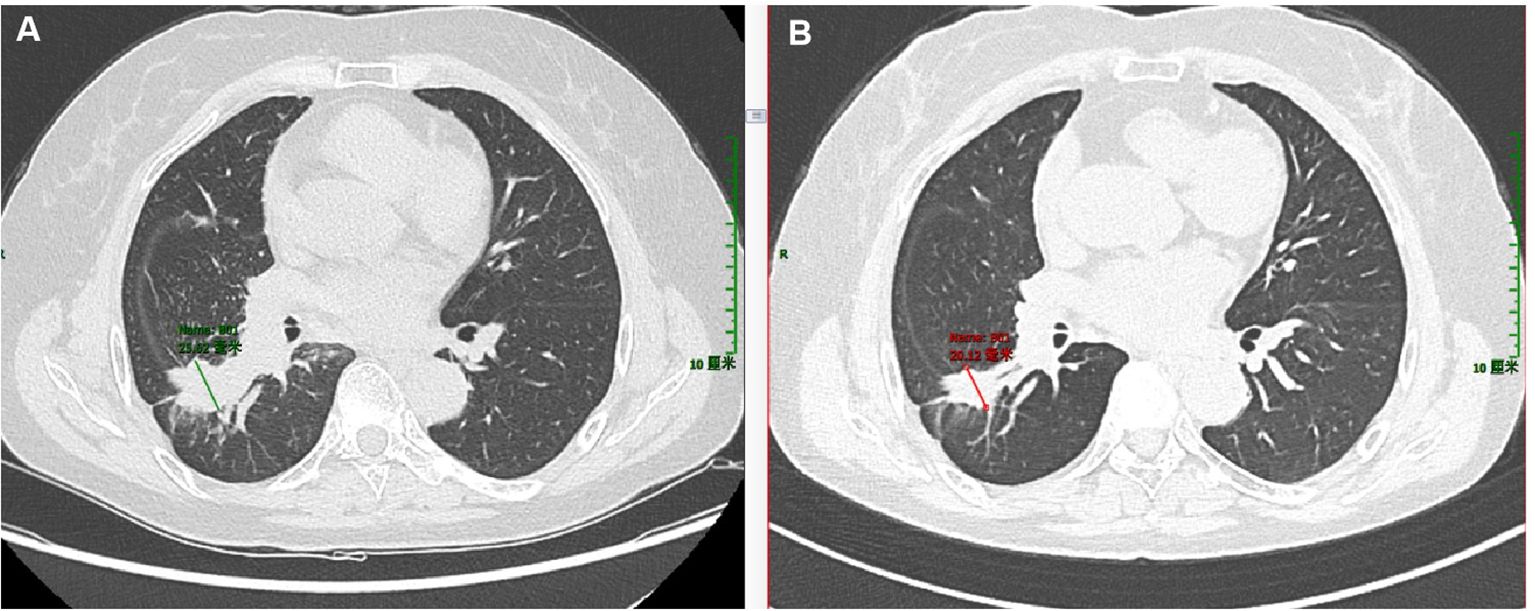

Objective: To investigate the clinical and pathological characteristics of patients with non-small cell lung cancer exhibiting coexistence of NTRK2 fusion and EGFR mutations. Methods: Clinical data as well as histopathological, immunohistochemical, and molecular pathological characteristics of two patients harboring both NTRK2 gene fusions and EGFR gene mutations were retrospectively analyzed, and relevant literature was also reviewed. Results: Both patients were women, aged 57 and 66 years, respectively. The two cases were diagnosed as invasive lung adenocarcinoma, and immunohistochemical staining showed that all tumor cells expressed CK7, Napsin A, TTF-1, and PD-L1. In Case 1, an EGFR mutation in the primary lung lesion, coexistence of NTRK2 fusion and EGFR mutation in liver metastases, and concurrent MET gene amplification and FGFR1 gene mutation were observed. In Case 2, the coexistence of NTRK2 fusion and EGFR mutation was detected in the primary lung lesion. The TMB and microsatellite status were classified as TMB-L and MSS, respectively, in both cases. Case 1 received osimertinib combined with savolitinib, had 33 months of follow-up, and achieved a partial response. Case 2 received furmonertinib and achieved a complete response. Conclusion: NTRK2 fusion coexisting with EGFR mutations is a rare molecular characteristic of non-small cell lung cancer, accompanied by positive PD-L1 expression, and may serve as a promising biomarker for targeted therapy.